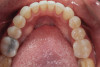

(4.) Preoperative occlusal view of upper arch.

Figure 4

A comprehensive examination was carried out, and preoperative photographs were taken (Figure 1 through Figure 4). The patient presented with fair oral hygiene and slight, generalized tissue inflammation. Caries and defective restorations were detected on teeth Nos. 4, 5, 13, and 14. The crown on tooth No. 12 was showing signs of leakage, and although the endodontic access cavity had been temporarily restored with composite, this endodontic re-treatment was acceptable and the tooth was otherwise symptom-free. Erosion was present on most of the posterior teeth and the cuspids, and abrasion was noted on teeth Nos. 4, 5, 10, 11, 20, 21, 22, 28, and 29. An examination of the patient's muscles, joints, and bite revealed no joint sounds, a normal range of motion, and negative joint load and immobilization tests.

The dentofacial examination revealed a low smile line with no incisor display when the lips were in repose. The anterior teeth were chipped and worn, and their overall color was darkened. The buccal corridors were deficient, and the failing crown on tooth No. 12 was visible in a full smile.